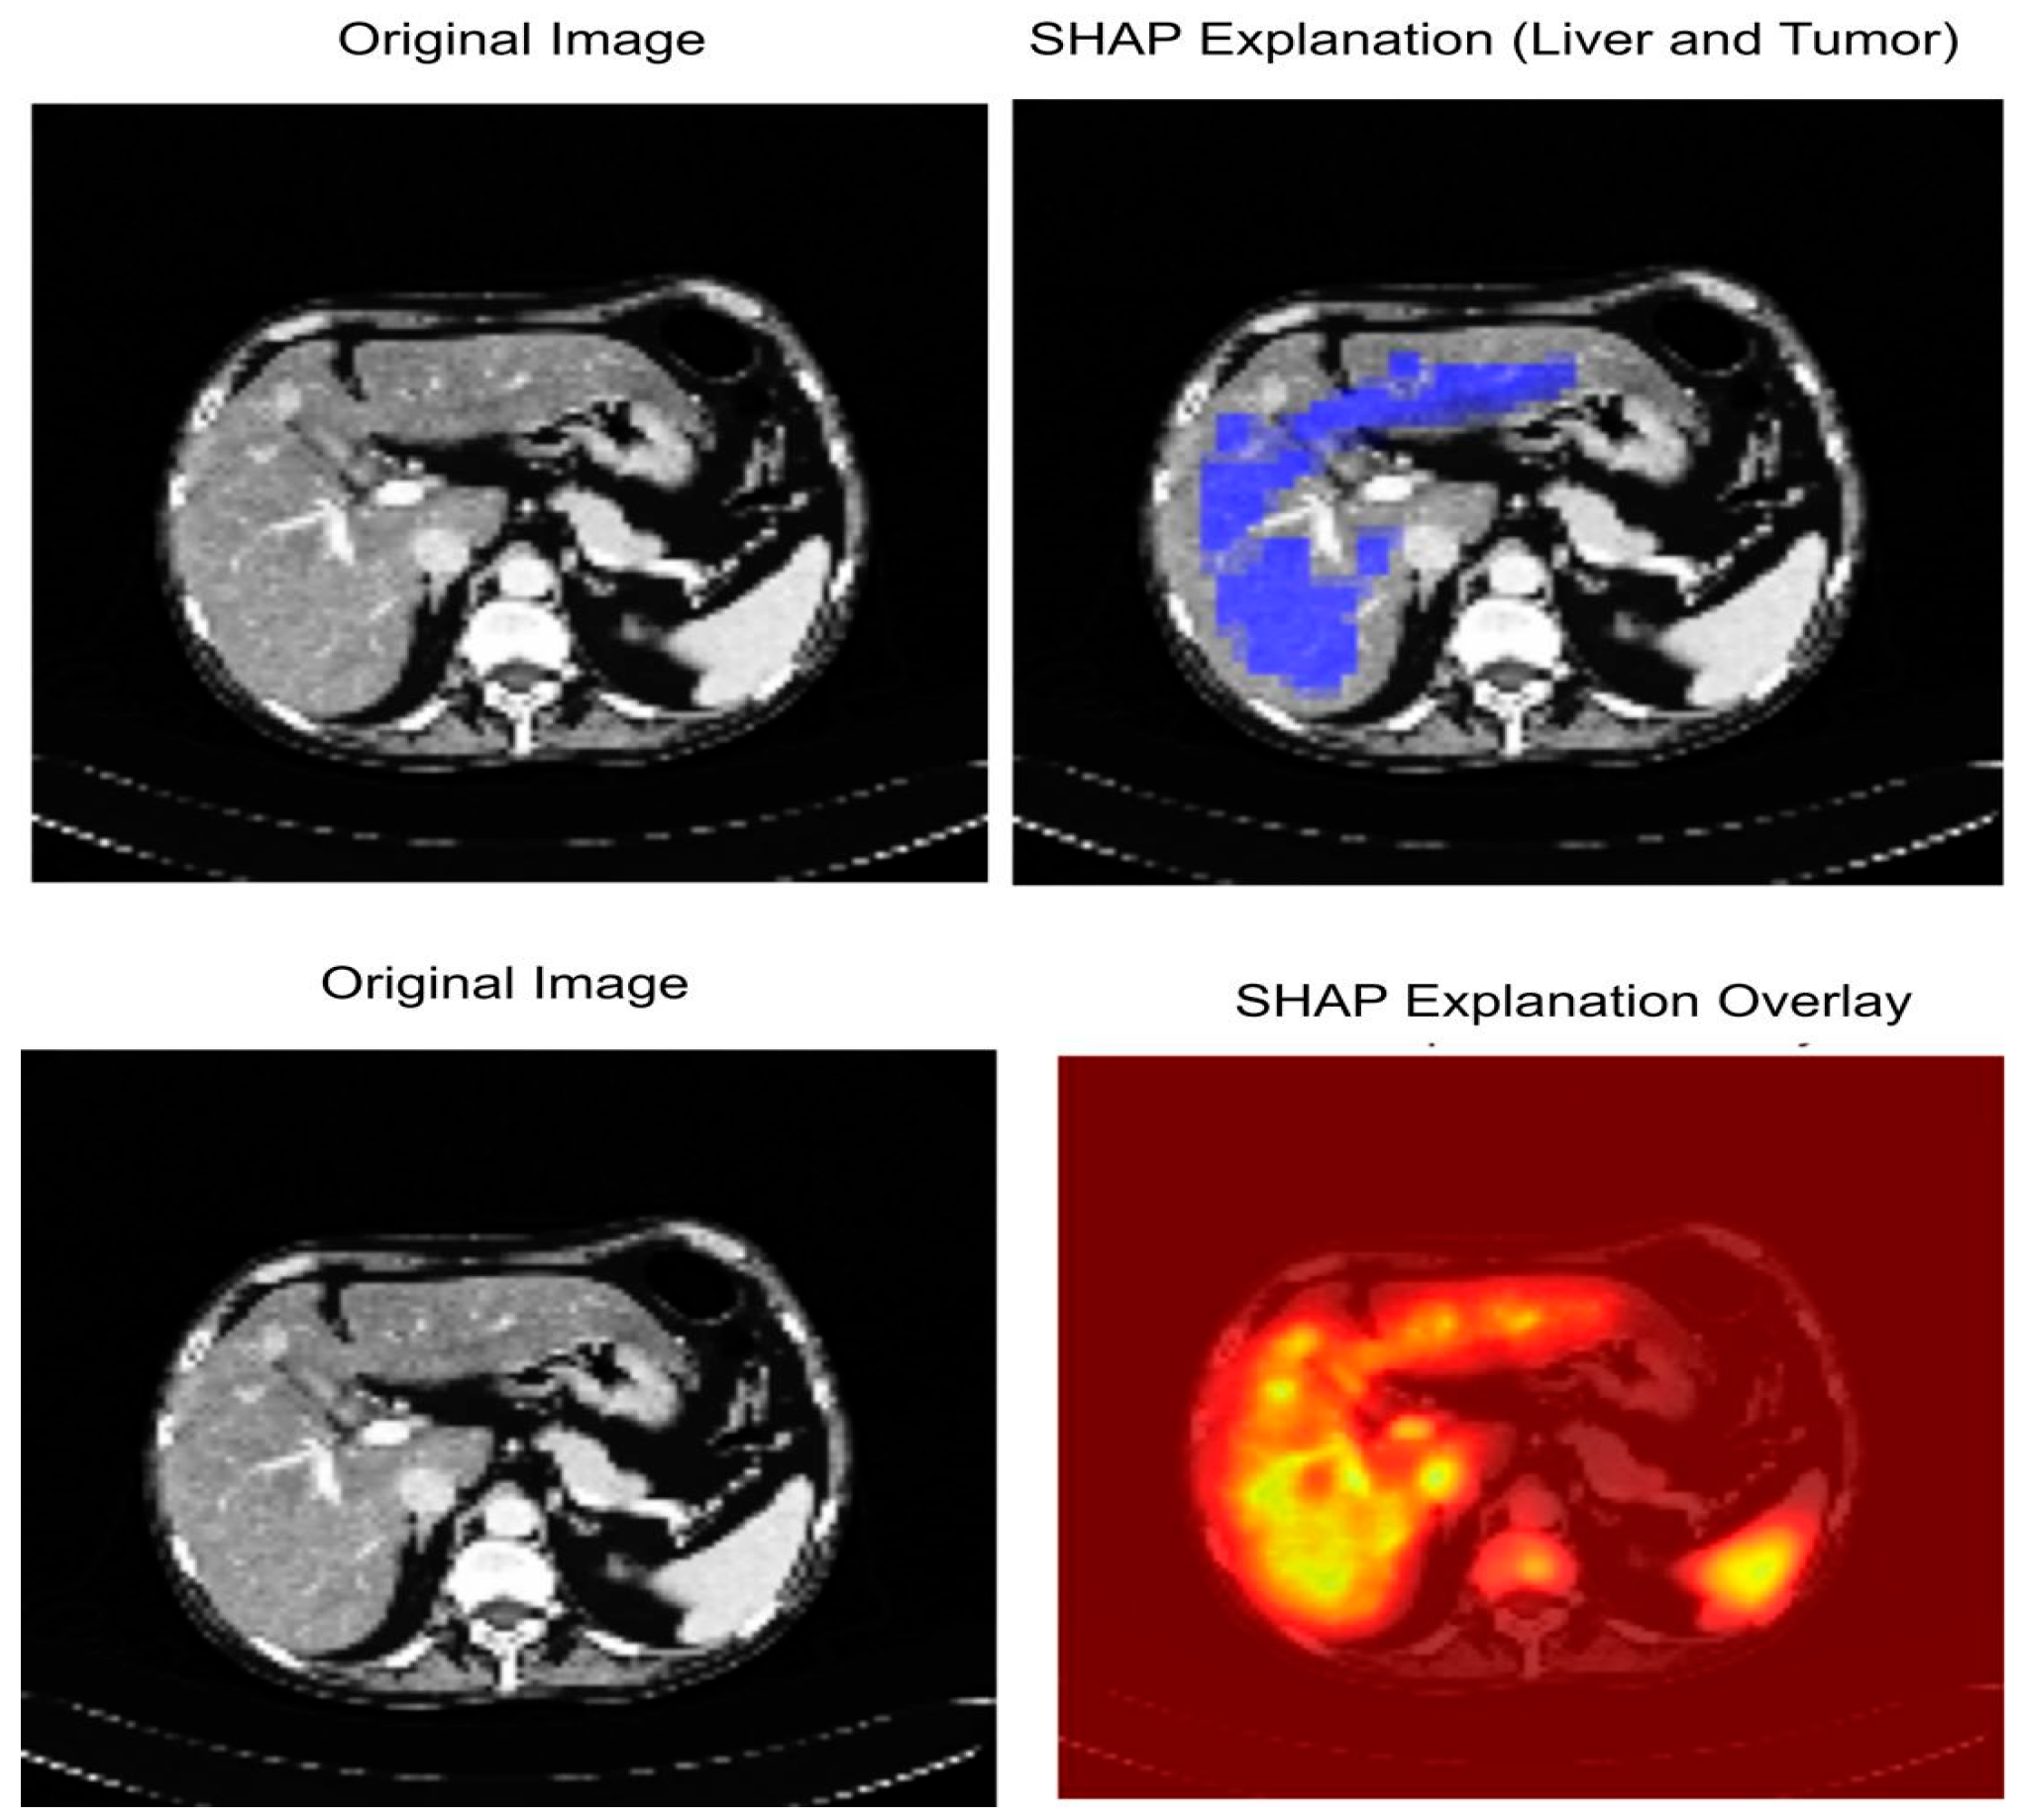

3.7. Explainable AI (XAI)

4.7. Explainable AI Analysis